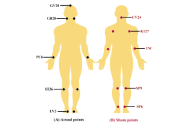

DOI: https://doi.org/10.37349/emed.2025.1001320 The effect of acupressure on anxiety, fatigue, and blood pressure in hemodialysis patients: a randomized controlled trial studyOpen AccessOriginal ArticleAim: The present study determined the effect of acupressure on anxiety, fatigue, and blood pressure in hemodialysis patients. Methods: This randomized controlled clinical trial study was co [...] Read more.Manizhe Nasirizade ... Hamidreza Bahrami-TaghanakiPublished: May 21, 2025 Explor Med. 2025;6:1001319

The effect of acupressure on anxiety, fatigue, and blood pressure in hemodialysis patients: a randomized controlled trial studyOpen AccessOriginal ArticleAim: The present study determined the effect of acupressure on anxiety, fatigue, and blood pressure in hemodialysis patients. Methods: This randomized controlled clinical trial study was co [...] Read more.Manizhe Nasirizade ... Hamidreza Bahrami-TaghanakiPublished: May 21, 2025 Explor Med. 2025;6:1001319